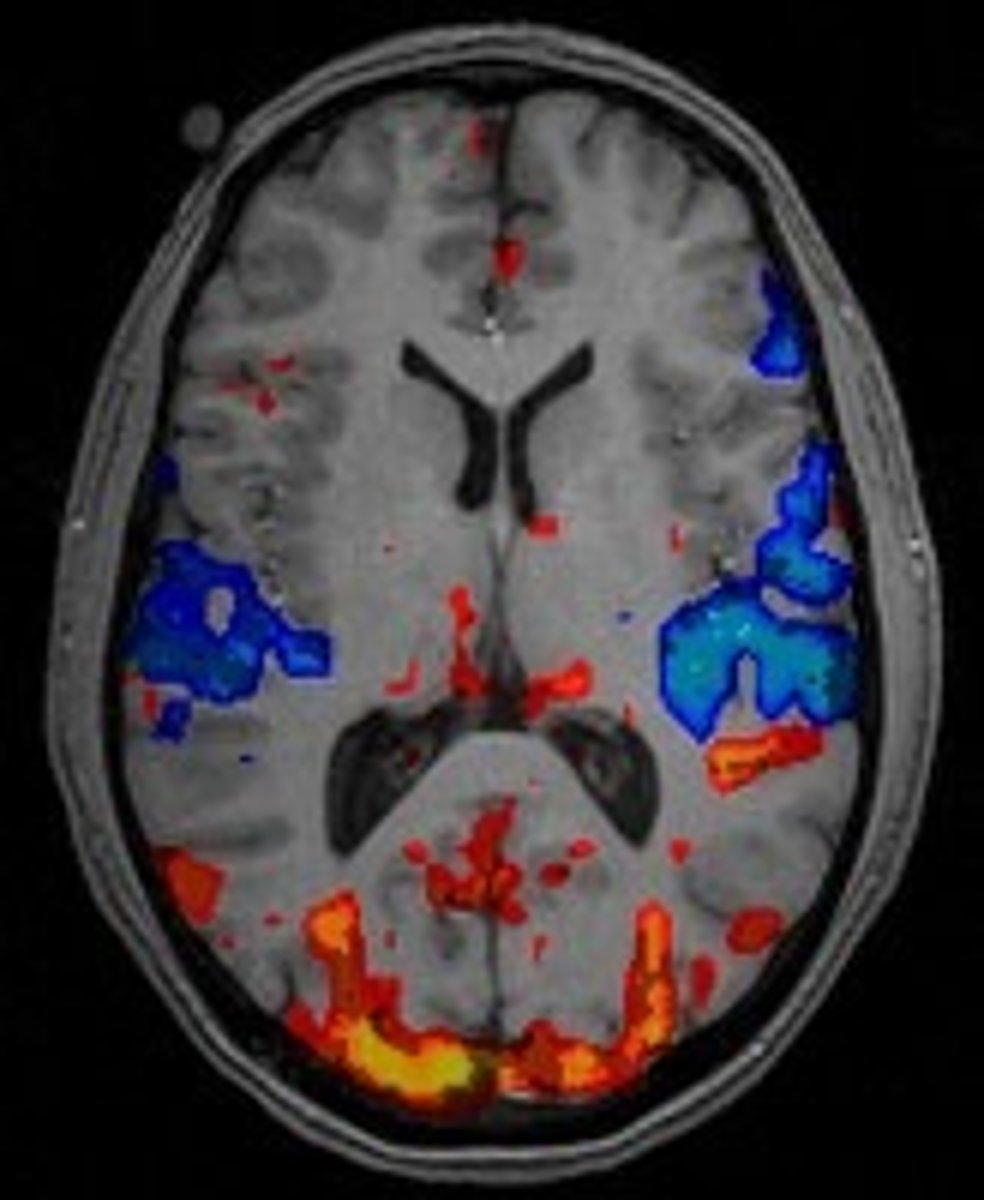

fMRI

Measures brain activity by detecting blood flow; shows both structure and activity.

MRI

Uses magnetic fields and radio waves to produce detailed images of brain structures.